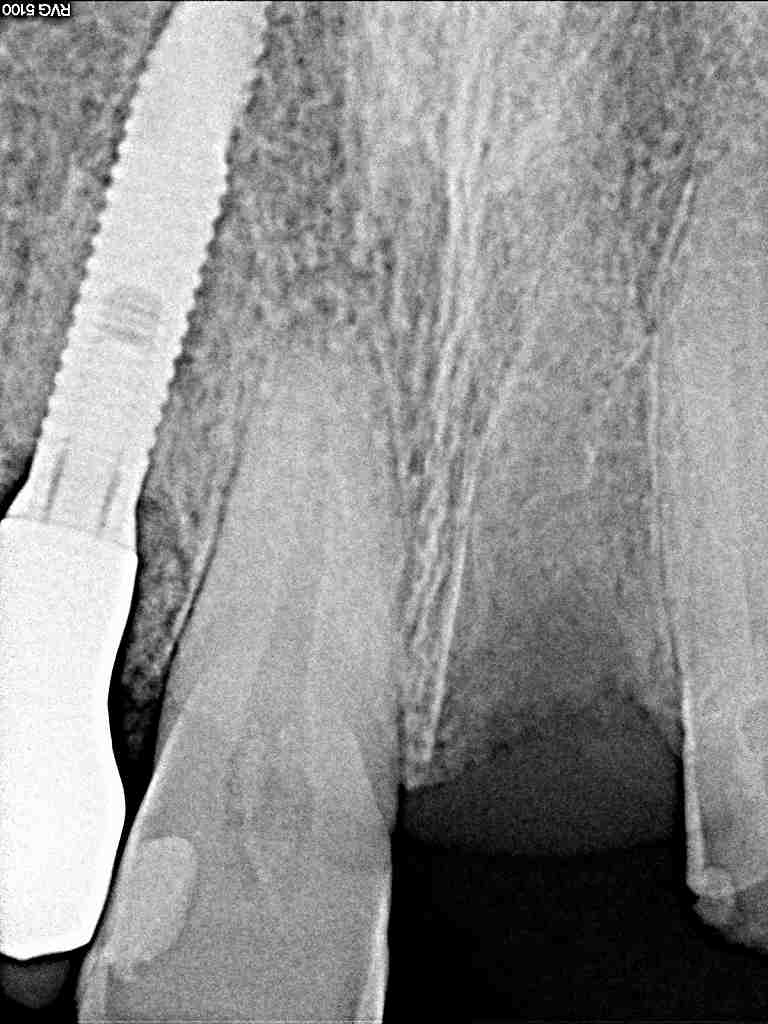

階段からこけて歯が抜けた 受傷から1週間後に治療|お知らせ |広島市安佐南区の歯科医院 階段からこけて歯が抜けた 受傷から1週間後に治療 トップ お知らせ・ブログ お知らせ 階段からこけて歯が抜けた 受傷から1週間後に治療 階段からこけて歯が抜けた 受傷から1週間後に治療 抜けた歯になります 歯根膜も乾き、再植は難しくなっていました 1週間このままにて過ごしたそうです 転勤先から帰られたときに受診 レントゲンにて ソケットもきれいです 麻酔をかけ補填材を入れてソケットプリザベーションをしていきました ブリッジになるかインプラントになるかわからないですが、、、 転勤もあり、何もなく5年が過ぎてしまいました 珍しいケースです 治療のタイミングを失いながら、このままで Web診療予約 初めての方へ 選ばれ続ける理由 院内設備について 歯が痛いしみる一般歯科 歯がぐらぐらする歯周病 健康な歯を保ちたい予防歯科 子供の虫歯予防をしたい小児歯科 銀歯をセラミックに審美歯科 白い歯を目指しませんか?ホワイトニング 矯正専門医がいるので安心矯正歯科 抜けた歯を補いたいインプラント・入れ歯 医院案内 スタッフ紹介 メリィハウス歯科クリニックオフィシャルホームページ ラベンダー歯科クリニックオフィシャルホームページ お知らせ・ブログ ホーム 診療科目 一般歯科 歯周病治療 予防治療 小児歯科 審美治療 ホワイトニング 矯正歯科 入れ歯・インプラント マウスピース矯正 初めての方へ 院長・スタッフ 設備紹介 医院案内・アクセス メニューを閉じる